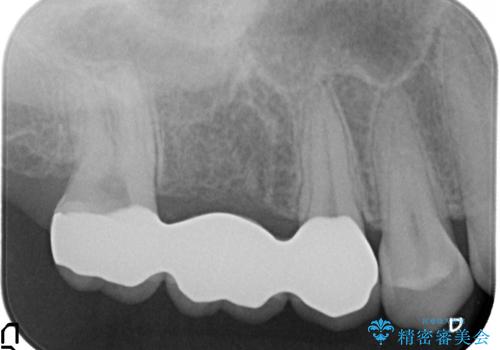

右上6番目の歯は虫歯が深く、保存が難しかったため抜歯しました。

その後歯茎や骨の回復を待ち、オールセラミッククラウンのブリッジによる補綴を行いました。